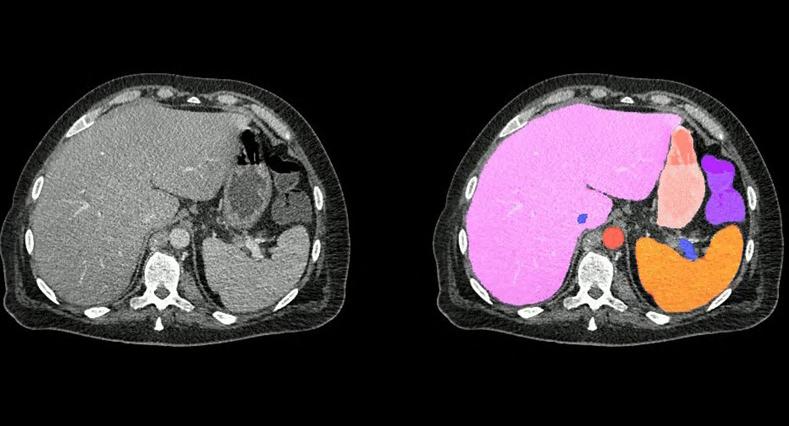

AI-Powered Abdomen Map Enables Early Cancer Detection

Ateamof researchers from around the globe, led by Johns Hopkins University (Baltimore, MD, USA; www.jhu.edu), has harnessed AI to create the most extensive and comprehensive dataset of abdominal organs to date, designed to help radiologists quickly and accurately identify tumors and other medical conditions. AbdomenAtlas, which is the largest abdominal CT dataset available, also provides a valuable benchmark that allows other research groups to test the accuracy of their medical segmentation algorithms.

Image: Two abdominal CT scan slices, standard on the left and AbdomenAtlas’ organ segmentation on the right (Photo courtesy of Johns Hopkins University)